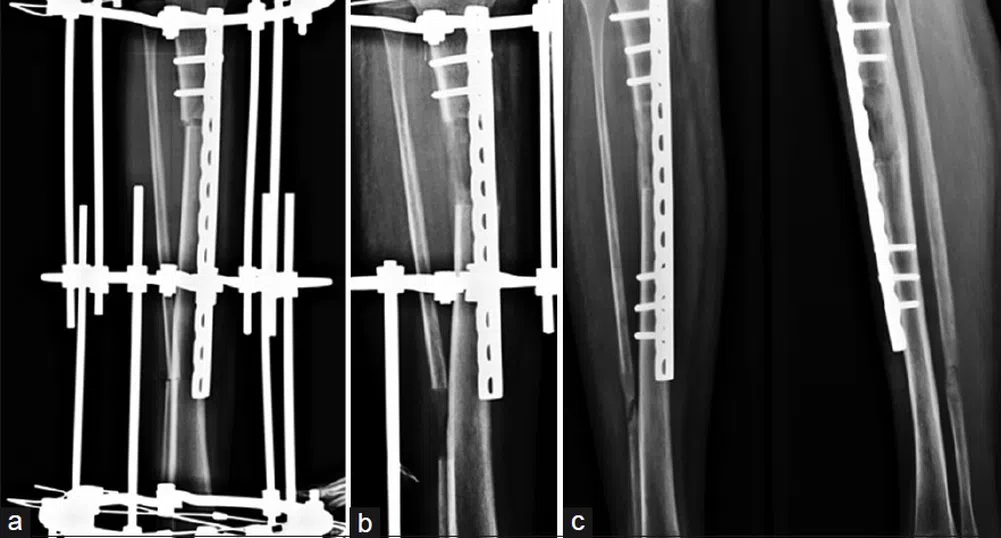

24-годишната жена от Кота, Западна Индия, е посещавала доктор Амар Сарин, хирург ортопед в Делхи, който я прави с осем сантиметра по-висока - процедура, която включва чупенето на кости на краката и носенето на шина, докато проходи отново, пише Guardian.

Операцията за удължаване на крайниците се прави за първи път през 50-те години в малък руски град на име Курган в Сибир. Пионерът в тази област е поляк на име Гаврийл Илизаров. Той бил смятан за шарлатанин, но впоследствие става известен като “вълшебникът от Курган”, след като извършва няколко такива операции, в това число и на олимпийски шампион на висок скок.

Илизаров обаче не е възнамерявал неговата техника да бъде използвана за пластични цели; неговата работа е била насочена към хора, които са претърпели инциденти или пък били родени с крайници с различна дължина.

Сега спорната техника на Илизаров се използва от хирурзи в цяла Индия, макар и с доста модерни изменения, които имат за цел да я направят по-бърза и безболезнена. Сарин, който е международно признат за уменията си в тази област, казва, че първоначално е имал проблеми с етичната страната на нещата. “Чудех се дали това, което правя, е правилно, но когато видях колко много се подобрява самочувствието на пациентите, реших да продължа,” казва той.